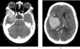

Temporal lobe hematoma

Intracerebral hemorrhage (ICH), also known as cerebral bleed and intraparenchymal bleed, is a sudden bleeding into the tissues of the brain, into its ventricles, or into both. It is one kind of bleeding within the skull and is one kind of stroke.Symptoms can include headache, one-sided weakness, vomiting, seizures, decreased level of consciousness, and neck stiffness. [Source: Wikipedia ]